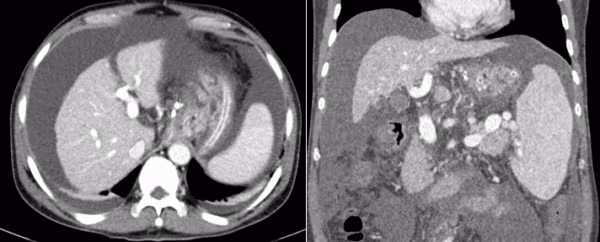

Hình ảnh trước và sau khi đặt stent TIPS trong gan và nút tắc các búi giãn tĩnh mạch thực quản - Ảnh BVCC

Sau khoảng 1 giờ can thiệp, các bác sĩ đã đặt một stent phủ vào trong gan, làm giảm áp lực tĩnh mạch cửa và nút tắc hoàn toàn các búi giãn tĩnh mạch thực quản.

Sau 2 ngày theo dõi, người bệnh đã hoàn toàn ổn định, đi ngoài phân vàng, tình trạng chướng bụng giảm đáng kể, các xét nghiệm cải thiện tốt và được ra viện điều trị theo phác đồ tại nhà.